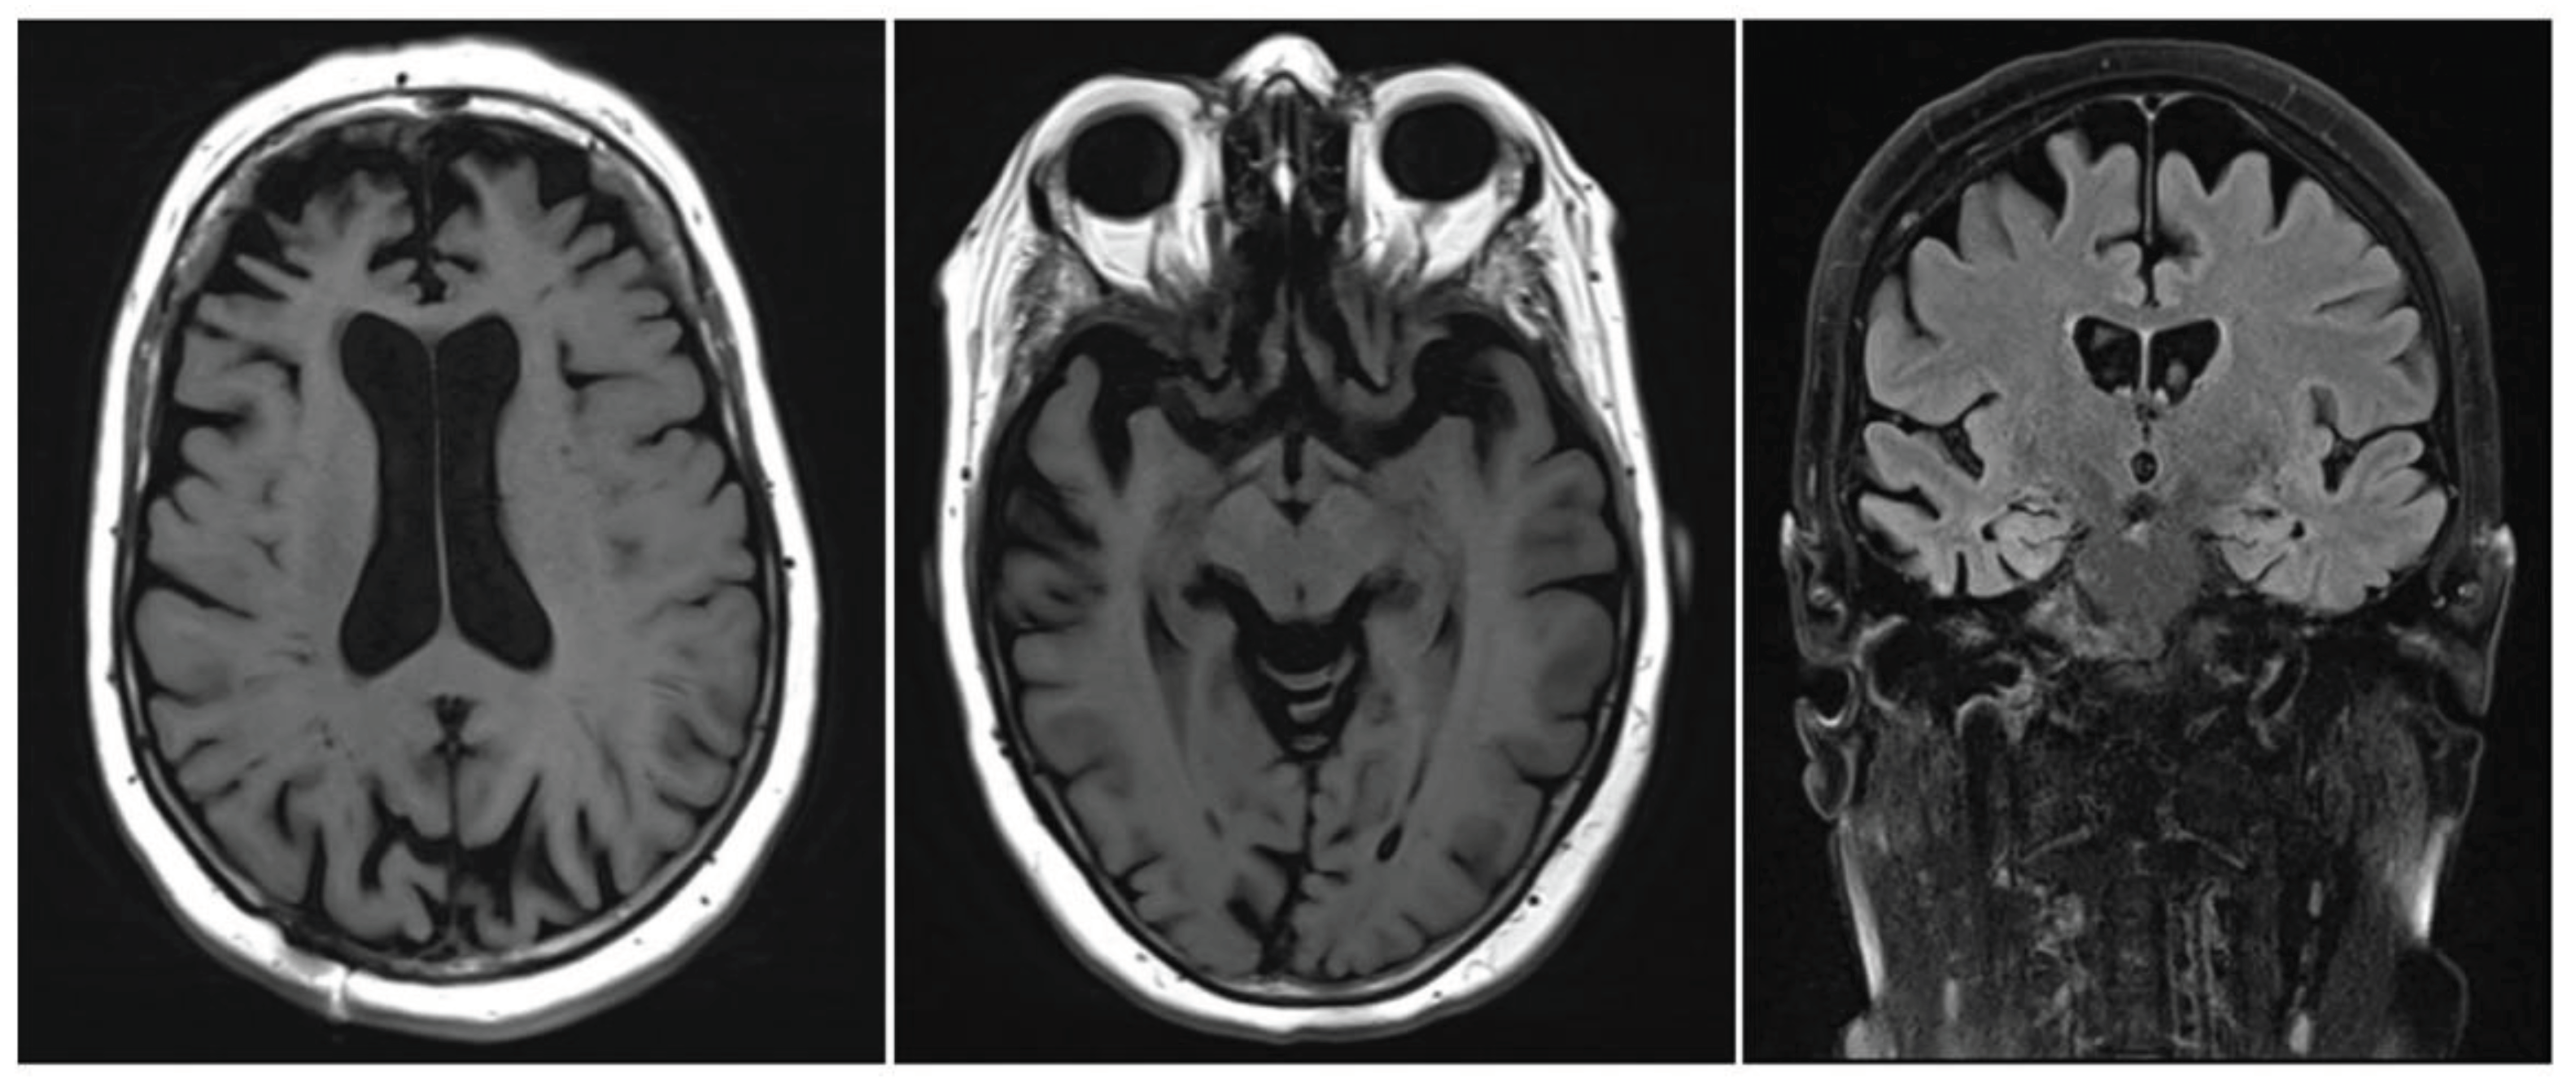

- Smith, E.E. Clinical presentations and epidemiology of vascular dementia. Clin. Sci. 2017, 131, 1059–1068. [Google Scholar] [CrossRef]

- O'Brien, J.T.; Thomas, A. Vascular dementia. Lancet 2015, 386, 1698–1706. [Google Scholar] [CrossRef] [PubMed]